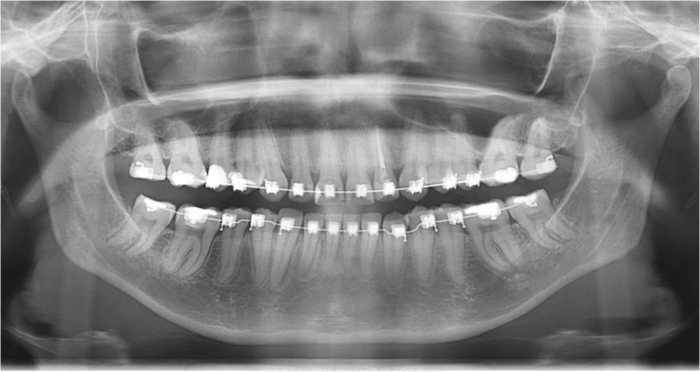

Raio x inicial

Raio x final